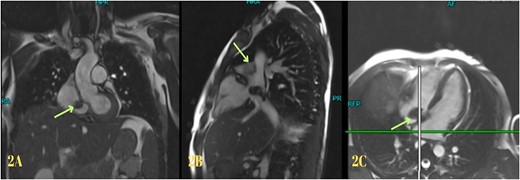

Blood investigations revealed leukocytosis and thrombocytopenia (Table 1). His electrocardiogram (ECG) showed a normal sinus rhythm, and chest X-ray revealed bilateral infiltrates. A high-resolution computed tomography (HRCT) scan of the chest was done in February 2020, which showed multiple patchy pulmonary infiltrates in the upper and lower lobe of the left lung, the middle lobe and the lower lobe of the right lung (Fig. 1). An air bronchogram was noted within the area of consolidation of the middle lobe of the right lung. Also, heavy calcification of irregular areas within the right atrium, extending up to the opening of the IVC, was noted. We did a further investigation with transthoracic echocardiography, which revealed an echogenic mass in the right atrium of 3.0 ✕ 1.9 cm2, most likely a thrombus. Following this, we investigated the patient with cardiac MRI, which showed a large irregular mass of 25 ✕ 18 mm2 in the right atrium attached to the interatrial septum and extending to the IVC, most likely myxoma with superimposed thrombus (Fig. 2).

Usually, these tumours are diagnosed incidentally while evaluating the cardiac lesion in a patient [1]. Diagnosis can be made based on clinical, imaging and histopathology findings [3, 7]. Imaging modalities such as HRCT, echocardiography and cardiac MRI can aid in diagnosis [1, 3, 7]. Typically, histopathology can reveal polygonal, spindle and stellate cells in a myxomatous background [10]. Radiological investigations such as chest x-ray, HRCT, and cardiac MRI were used to rule out differentials suggesting cardiac myxoma. In addition, the histopathology of the resected specimen also suggested cardiac myxoma. Hence, we made a diagnosis of cardiac myxoma. Early diagnosis and intervention of cardiac myxomas are associated with a good prognosis [7, 8]. Surgical intervention is the mainstay of management for cardiac myxoma [1]. Hence, we managed the patient with complete tumour resection, and the patient improved symptomatically.